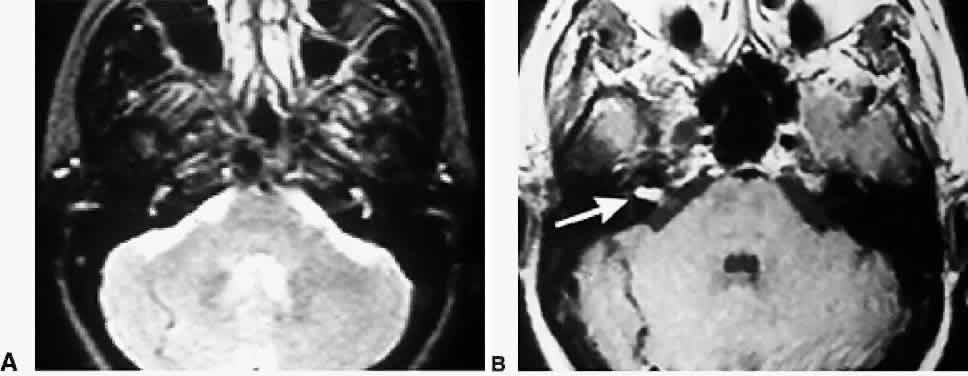

Acoustic neuroma is a benign tumor of the myelin sheaths of the vestibular nerve (VIII) and usually is characterized by unilateral hearing loss or tinnitus. Rarely does it cause vertigo or disequilibrium. Audiography shows features consistent with a retrocochlear process, which consists of poor speech discrimination relative to the degree of tone loss and recruitment in which increments in tone intensity cause a higher than expected increase in perceived tone loudness. The diagnostic procedure of choice for acoustic neuroma is gadolinium-enhanced MRI sections of the posterior fossa that include the VIIIth nerve and other cerebellopontine angle structures (Fig. 8). Surgery is the treatment of choice, either by middle cranial fossa approaches (for tumors confined to the internal auditory canal, with usable hearing), by suboccipital craniotomy (for large tumors or those adherent to the brainstem, with usable hearing), or by a translabyrinthine approach (for small tumors, with no usable hearing).31 With questionable or small intracanalicular tumors, especially in elderly patients or in those in poor medical condition, watchful waiting is prudent, with neuroimaging repeated at 6- to 12-month intervals. Focal radiosurgery may be ideal for recurrent tumors and for patients in poor medical condition who cannot tolerate posterior fossa surgery.31 Tumor control is achieved in 95% of patients, but approximately 25% to 30% develop 5th and 7th cranial nerve loss and hearing loss caused by involvement of the vascular supply.31,32

Fig. 8. Small acoustic neuroma revealed in an enhanced MRI of the head. Left. Axial T2 MRI through the cerebellar pontine angle. Right. Same section in a gadolinium-enhanced T1 MRI. The intracanalicular portion of the VIIIth nerve on the right side is enhanced (arrow) consistent with an acoustic neuroma.